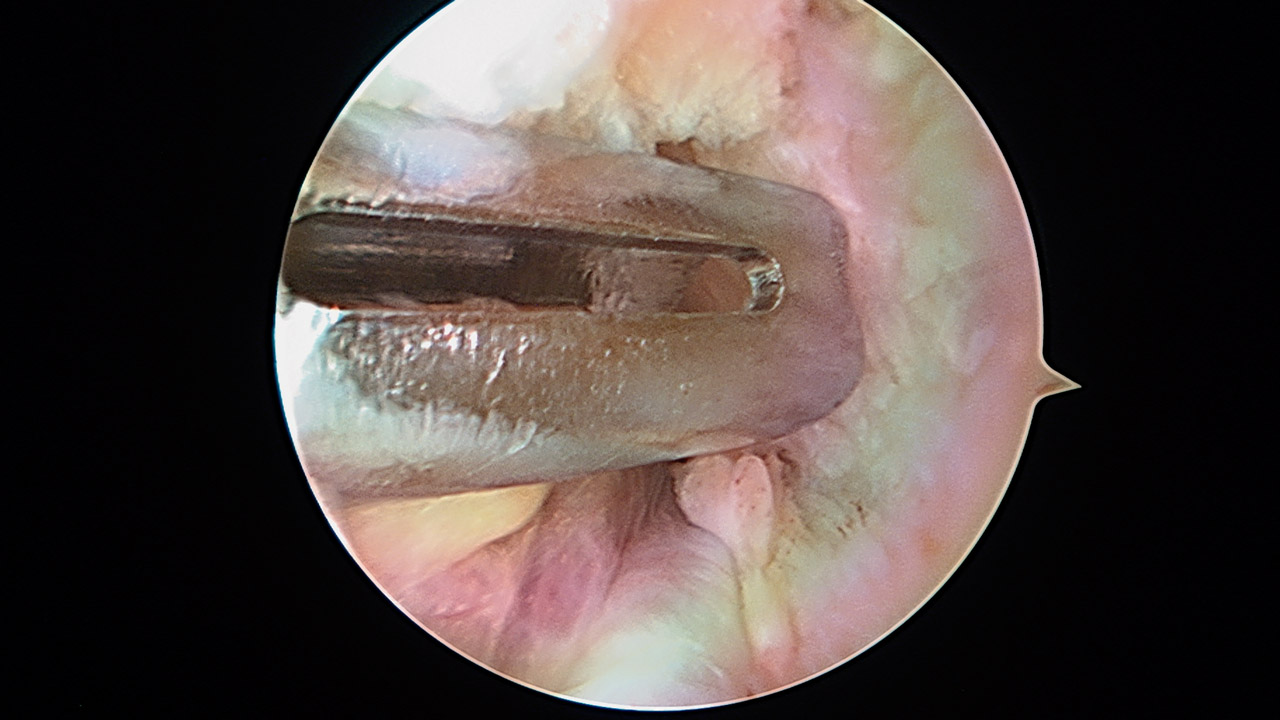

Presentamos una técnica quirúrgica artroscópica para los casos de inestabilidad traumática o atraumática de hombro, con hiperlaxitud multidireccional asociada, en los que hayan fracasado los tratamientos conservadores u otras técnicas quirúrgicas de plicatura capsular, y no presenten déficit óseo importante. Consiste en la plicatura del ligamento glenohumeral inferior (anteroinferior y posteroinferior) y la realización de una ligamentoplastia de refuerzo anterior artroscópica con aloinjerto en disposición transubescapular.

We present an arthroscopic surgical technique for cases of traumatic instability or atraumatic of the shoulder, with associated multidirectional hyperlaxity in which conservative treatments have failed, or other surgical techniques of plication capsular, and do not present major bone deficits. It consists of the plication of the lower glenohumeral ligament (anteroinferior and posteroinferior) and the accomplishment of an arthroscopic anterior reinforcement ligamentoplasty with allograft in a trans-scapular arrangement.